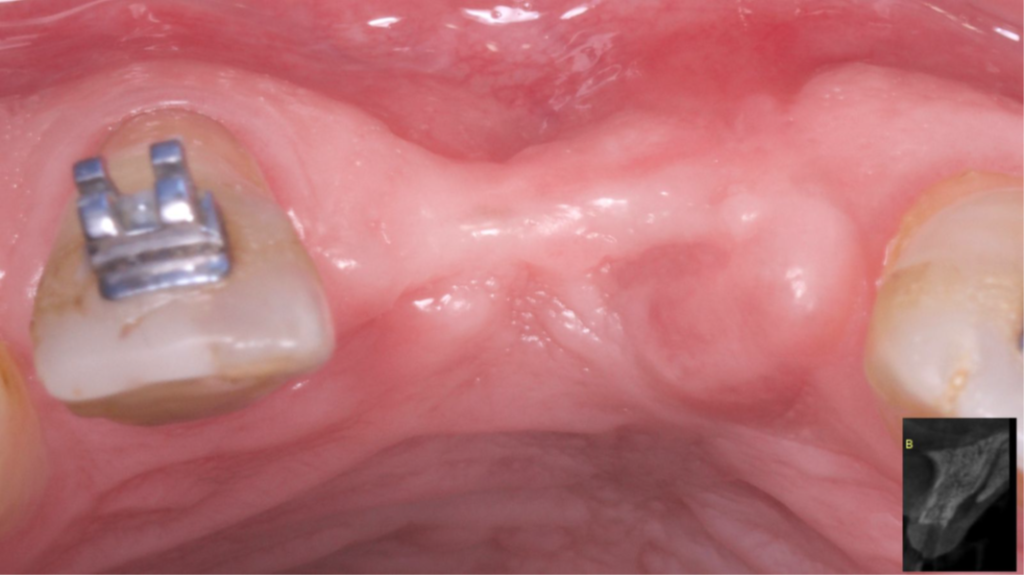

Paciente do sexo masculino encaminhado pela Ortodontia para a instalação de um implante ao nível do dente 1.1 (Figura 1), com diastemas mésio-distais de 2mm, para utilização do implante como ancoragem absoluta e melhor andamento da movimentação ortodôntica.